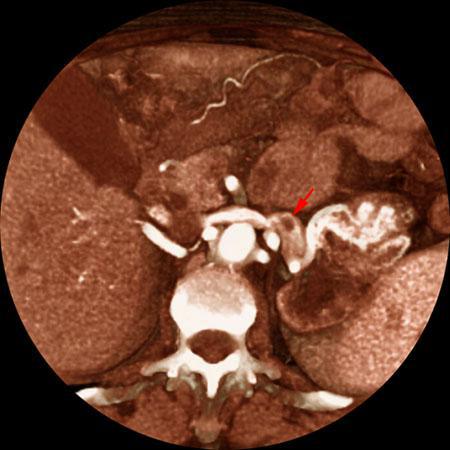

Tumor renal con trombosis venosa

VR seccional. Visión axial caudal. Defecto de replección en la vena renal izquierda (flecha) correspondiente a un trombo tumoral